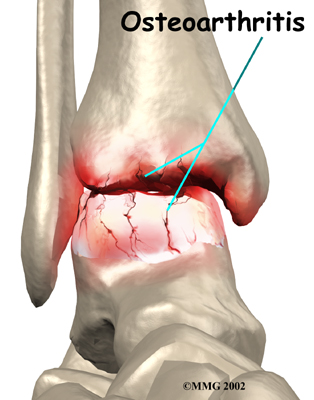

Injury to a joint, such as a bad sprain or fracture, can cause damage to the articular cartilage. The cartilage can be bruised when too much pressure is exerted on it. This damages the cartilage, although if you look at the surface it may not appear to be any different. The injury to the material doesn't show up until months later. Sometimes the cartilage surface is damaged even more severely, and pieces of the cartilage are ripped from the bone. These pieces do not heal back and usually must be removed from the joint surgically. If not, they may float around in the joint, causing the joint to catch and be painful. These fragments of cartilage may also do more damage to the joint surface.

Once this cartilage is ripped away, it does not normally grow back. Unlike bone, holes in the surface are not simply replaced by the cartilage tissue around the hole. Instead the defects are filled with scar tissue. The scar tissue that forms is not nearly as good a material for covering joint surfaces as the cartilage it replaces. It just can't support weight and isn't smooth like true articular cartilage.

Over many years this imbalance in the joint mechanics can lead to damage to the articular surface. Since articular cartilage cannot heal itself very well, the damage adds up. Finally, the joint is no longer able to compensate for the increasing damage, and it begins to hurt. The damage occurs well before the pain begins.

When OA has reached a very severe stage, the bone itself under the articular cartilage may become worn away. This can lead to increasing deformities around the joint. In the final stages, the alignment of the bones can begin to form odd angles where they meet at the joint.